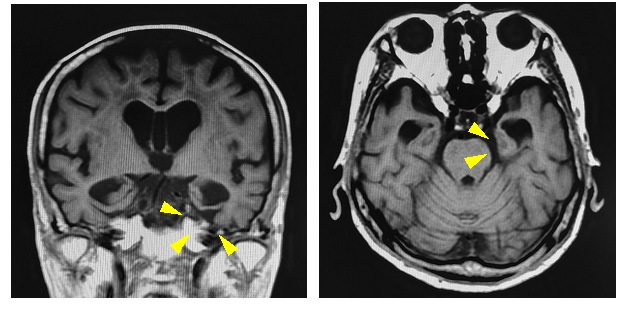

図2 嗜銀顆粒性認知症患者のMRI冠状断・軸位断画像 左優位に迂回回の萎縮を認める※当院例